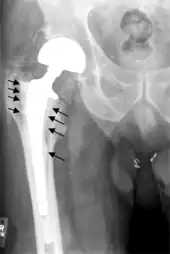

Fracture

Intraoperative fractures may occur. After surgery, bones with internal fixation devices in situ are at risk of periprosthetic fractures at the end of the implant, an area of relative mechanical stress. Post-operative femoral fractures are graded by the Vancouver classification.